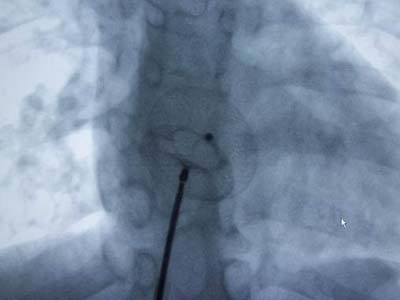

Carto三維定向標測系統指導下房顫射頻消融術